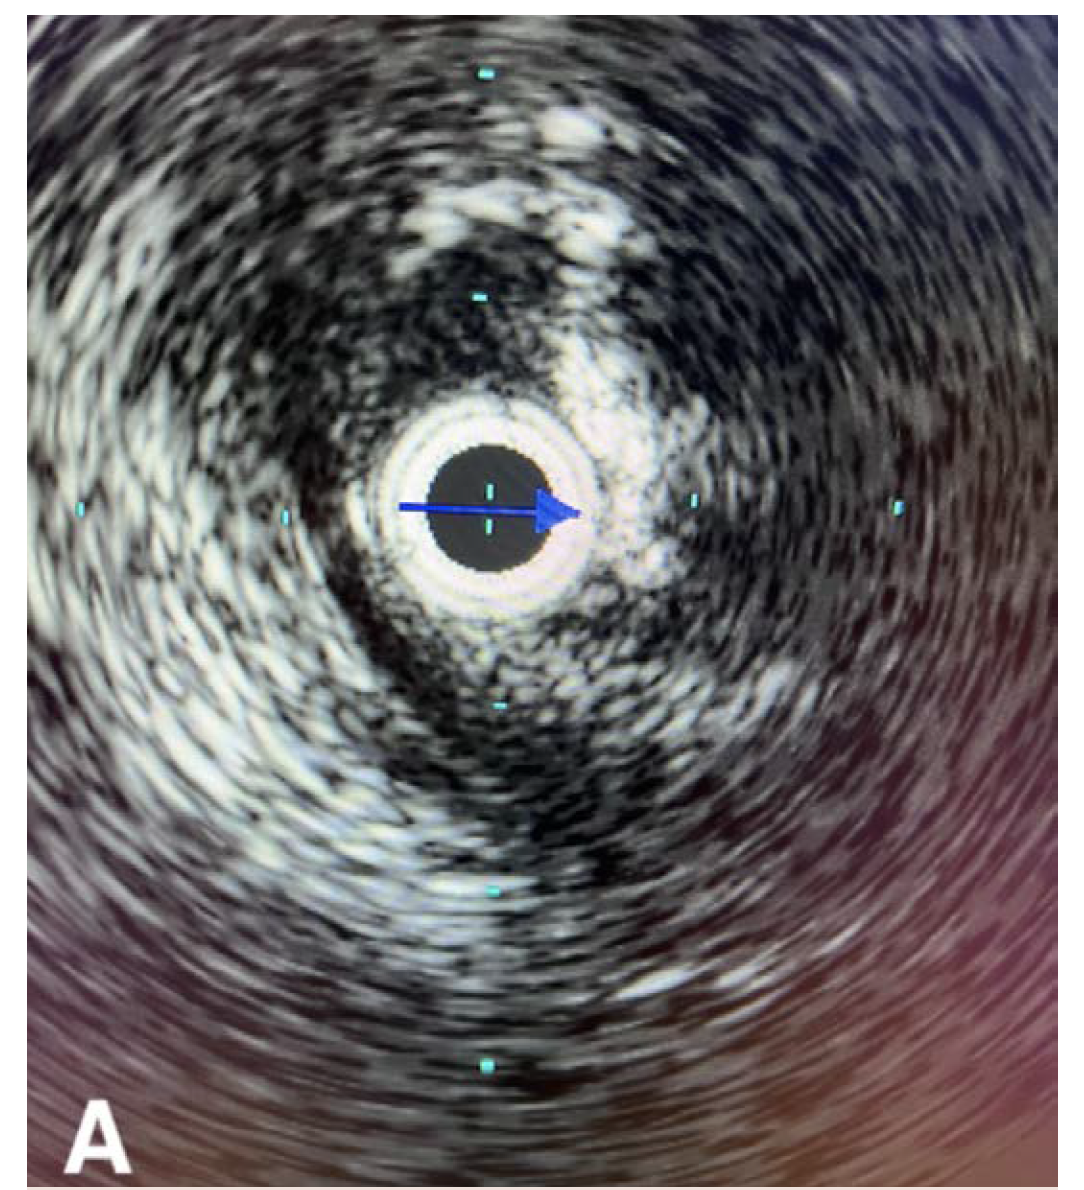

The patient underwent an initial catheter-directed diagnostic angiogram that revealed a 99% stenosis of the left CFA. The lesion was successfully transversed, and a 7 Fr 45-cm sheath was placed in the left external iliac artery. Intravascular ultrasound (IVUS) was performed over a 0.014" wire (Figure 1A), which demonstrated near occlusion of the CFA with heavy calcium burden. An 8-mm x 60-mm Shockwave balloon was then inflated to 4 atm, and 10 cycles were used to treat the CFA and proximal superficial femoral artery (Figure 1B). Completion angiogram showed an excellent result, with complete resolution of the calcific disease and no residual stenosis (Figure 1C). IVUS was performed at the end, which showed more than 80% luminal expansion after IVL treatment (Figure 1D). The patient was awakened from monitored anesthesia care and discharged from the postanesthesia care unit to home the same day.